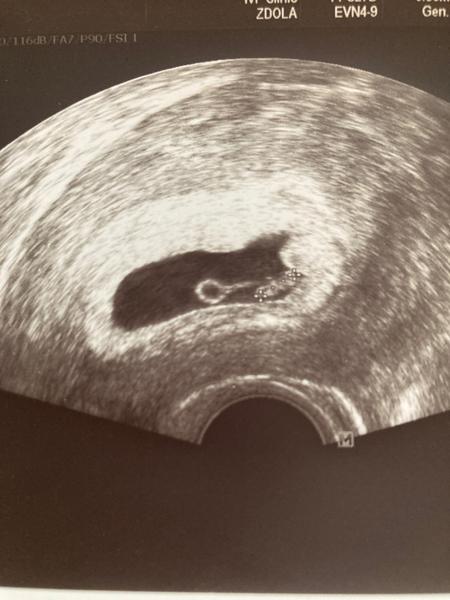

Ahojte. Na poslednej kontrole (6+5) mi gynekológ povedal, že je možnosť, že čakám dvojičky, nebolo to úplne jasné, že uvidíme na ďalšej kontrole. O mesiac! Och! Stále na to myslim, celý deň chodím kukať na fotku a rozmýšľam ako to dopadne. Niečo som aj hladala, ale našla som samé jasné sona, že sú dve. Mali ste niektorá takéto nie úplne jasné sono a boli to naozaj dvojičky? Ďakujem za odpovede 🙂💛

Pridávam fotku.

@lesnajahodka a nemohol to byt zltkovy vak? tiez sa mojej dr v prvom momente zdalo, ze su dve, ale hned sa opravila. Ten ultrazvuk je strasne slaby… no stretla som sa aj s tym, ze dr nema ziadny 🤷‍♀️ Tak lepsie slaby, ako ziadny 😀

@petricka22 o zltkovom vaku nepadlo ani slovo, len, že sa vynára otázka dvojičiek, viac nič. Srdiečko už bilo áno 💛💛 a ako tak pozerám, fakt je strašne slabý 🤣

Ahojte. Tak čakáme jedno bábätko, vyzerá ok, troška väčšie na svoj týždeň tam sme doma radi 🙂 ďakujem že ste na mňa mysleli!